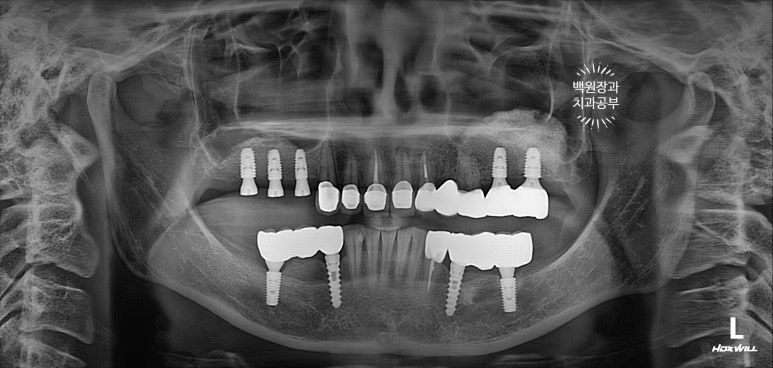

앞니와 어금니를 완성해두고 치과용 파노라마 엑스레이를 찍어봅니다.

새로 만들어진 보철물이 경계도 자연스럽게 잘 형성되어있고, 잇몸뼈와 조화롭게 완성이 되었네요.

그리고 오른쪽 어금니 임플란트도 2차수술을 해둡니다.

정말... 다시봐도 상악동 뼈이식술이 아주 적절히 잘 되어 딱 필요한만큼만 되어있네요. ㅎㅎ 이럴때 정말 뿌듯합니다. (변태같나요!?)

처음에 계획했던 5개의 어금니 임플란트와 3개짜리 지르코니아 브릿지 완성 후 정면 사진입니다.

가장 보람을 느끼게 되는 보철물 완성 후 치과용 파노라마 사진입니다.

정갈하게 치아가 완성되었네요... 이런 맛에 치과의사 하는 것이 아닌가 싶습니다.

뼈가 너~무 얇아 임플란트를 해드릴 수 없었던 송곳니 부위는 지르코니아 브릿지로 제작함으로써 자연스럽게 마무리 되었습니다.